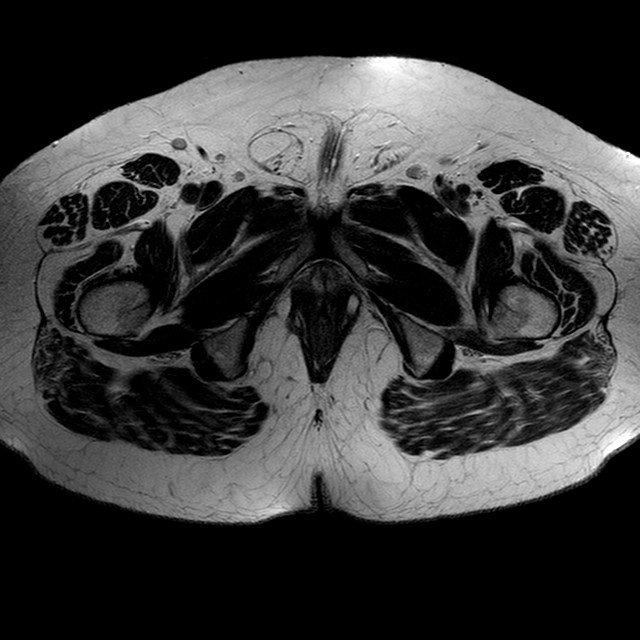

Esami: RMN BACINO

T2w TSE

Evidenti e simmetriche alterazioni osteofitosiche in regione coxo femorale con riduzione delle rime articolari. Degenerazione completa del cercine glenoideo. Non attuali segni di versamento articolare. Non segni di edema osseo che escludono attuale algodistrofia od osteonecrosi. Lieve e simmetrica riduzione del trofismo della muscolatura glutea.